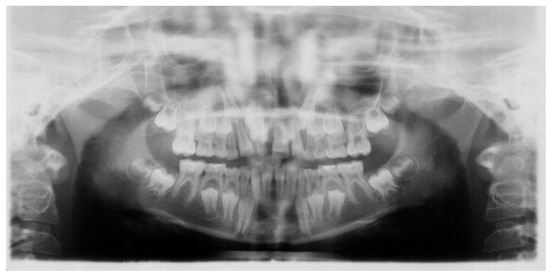

2. Case Report